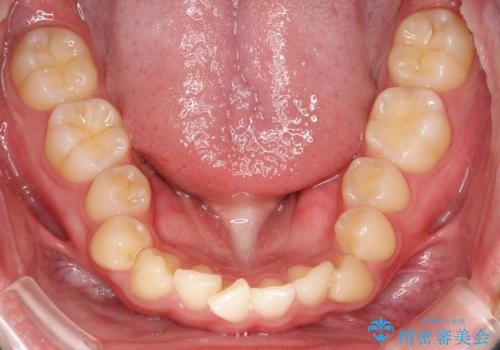

マウスピース矯正で前歯のガタツキを改善! 短期間で治療完了

- 前歯のガタツキが気になるとのことで来院されました。

マウスピース矯正で治療することとしました。

- 1年3ヶ月